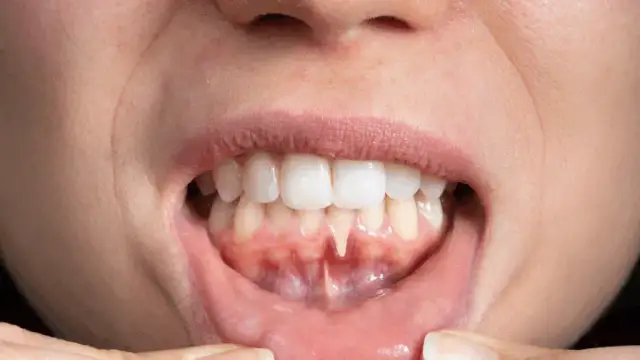

Jak zatamować krwawienie z dziąsła? Sprawdź natychmiastowe metody pierwszej pomocy, poznaj przyczyny i skuteczne sposoby zapobiegania problemowi.